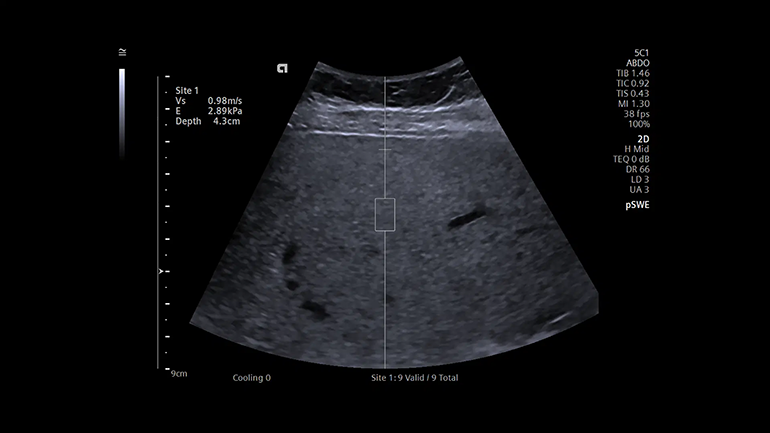

Технология качественного определения жесткости ткани в зоне интереса Point Shear Wave (pSWE). Технология точечной эластографии со сдвиговой волной позволяет получать воспроизводимую, надежную и подробную информацию о жесткости исследуемой ткани и помогает в оценке состояния, например, печени.

Технология качественного определения жесткости ткани в зоне интереса Point Shear Wave (pSWE). Технология точечной эластографии со сдвиговой волной позволяет получать воспроизводимую, надежную и подробную информацию о жесткости исследуемой ткани и помогает в оценке состояния, например, печени. Технология для определения скорости распространения поперечной волны при работе с линейными и конвексными датчиками. Двумерная эластография со сдвиговой волной (SWE). Это технология качественной и количественной диагностики, с помощью которой можно получить цветовые карты жесткости тканей молочной и щитовидной желез, используя для этого датчик 10L4, а также конкретные цифровые значения скорости распространения поперечной волны.